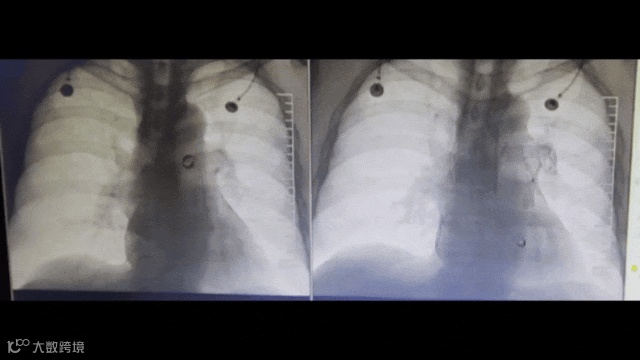

等待90秒后,连接抽吸器并形成负压,回撤取栓支架的同时旋转开关释放负压。最后,Tendvia®肺动脉取栓支架捕获和收集血栓进入抽吸导管,经负压抽吸同步的作用下,为患者顺利取出剩余血栓。

手术效果显著,患者术后心率恢复到正常水平。肺动脉血流动力学参数及氧合指数均获得显著改善,手术历时60分钟顺利完成。术后监测数据显示,患者生命体征平稳,血流动力学指标较术前明显改善。临床症状得到了有效缓解,患者安全返回病房。手术达到了预期治疗效果。

造影动图